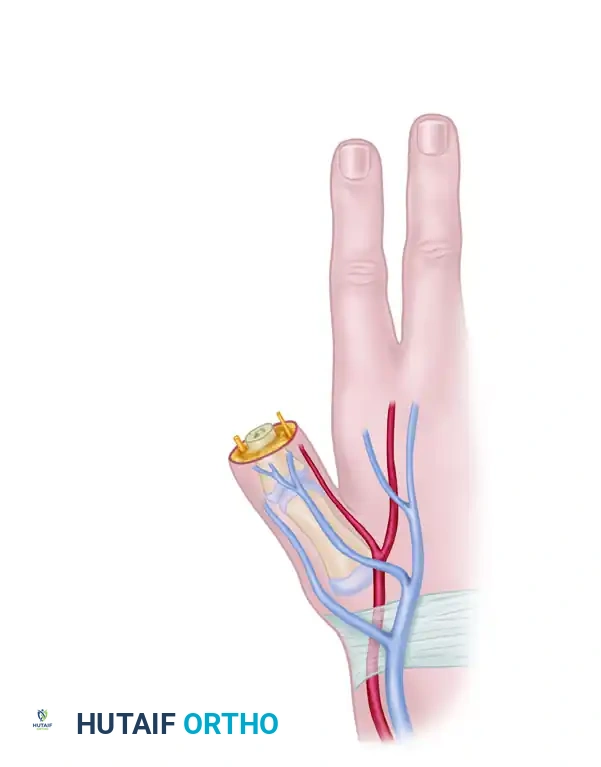

Incision and Exposure

Two primary areas on the hand require preparation: the amputation stump and the dorsoradial aspect of the hand (just distal to the anatomical snuffbox).

- With the pneumatic tourniquet inflated, make a longitudinal incision in the first web space between the first and second metacarpals.

- Dissect the thumb stump through a straight transverse incision across its tip, extending from midradial to midulnar.

- Elevate dorsal and volar subperiosteal flaps for approximately 1 cm to expose the bone end.

Neurovascular Preparation

- Veins: Dissect and mobilize two or more robust dorsal hand veins (cephalic vein tributaries).

- Arteries: Dissect between the first dorsal interosseous and the adductor pollicis muscles to identify and mobilize the princeps pollicis (first palmar metacarpal) artery. Mobilize this arterial pedicle proximally to the level of the proposed anastomosis.

- Nerves: Identify the superficial radial nerve dorsally. Volarly, expose and dissect the ulnar digital neuroma of the thumb. Excise the neuroma back to healthy fascicles just before the flap is ready for attachment.